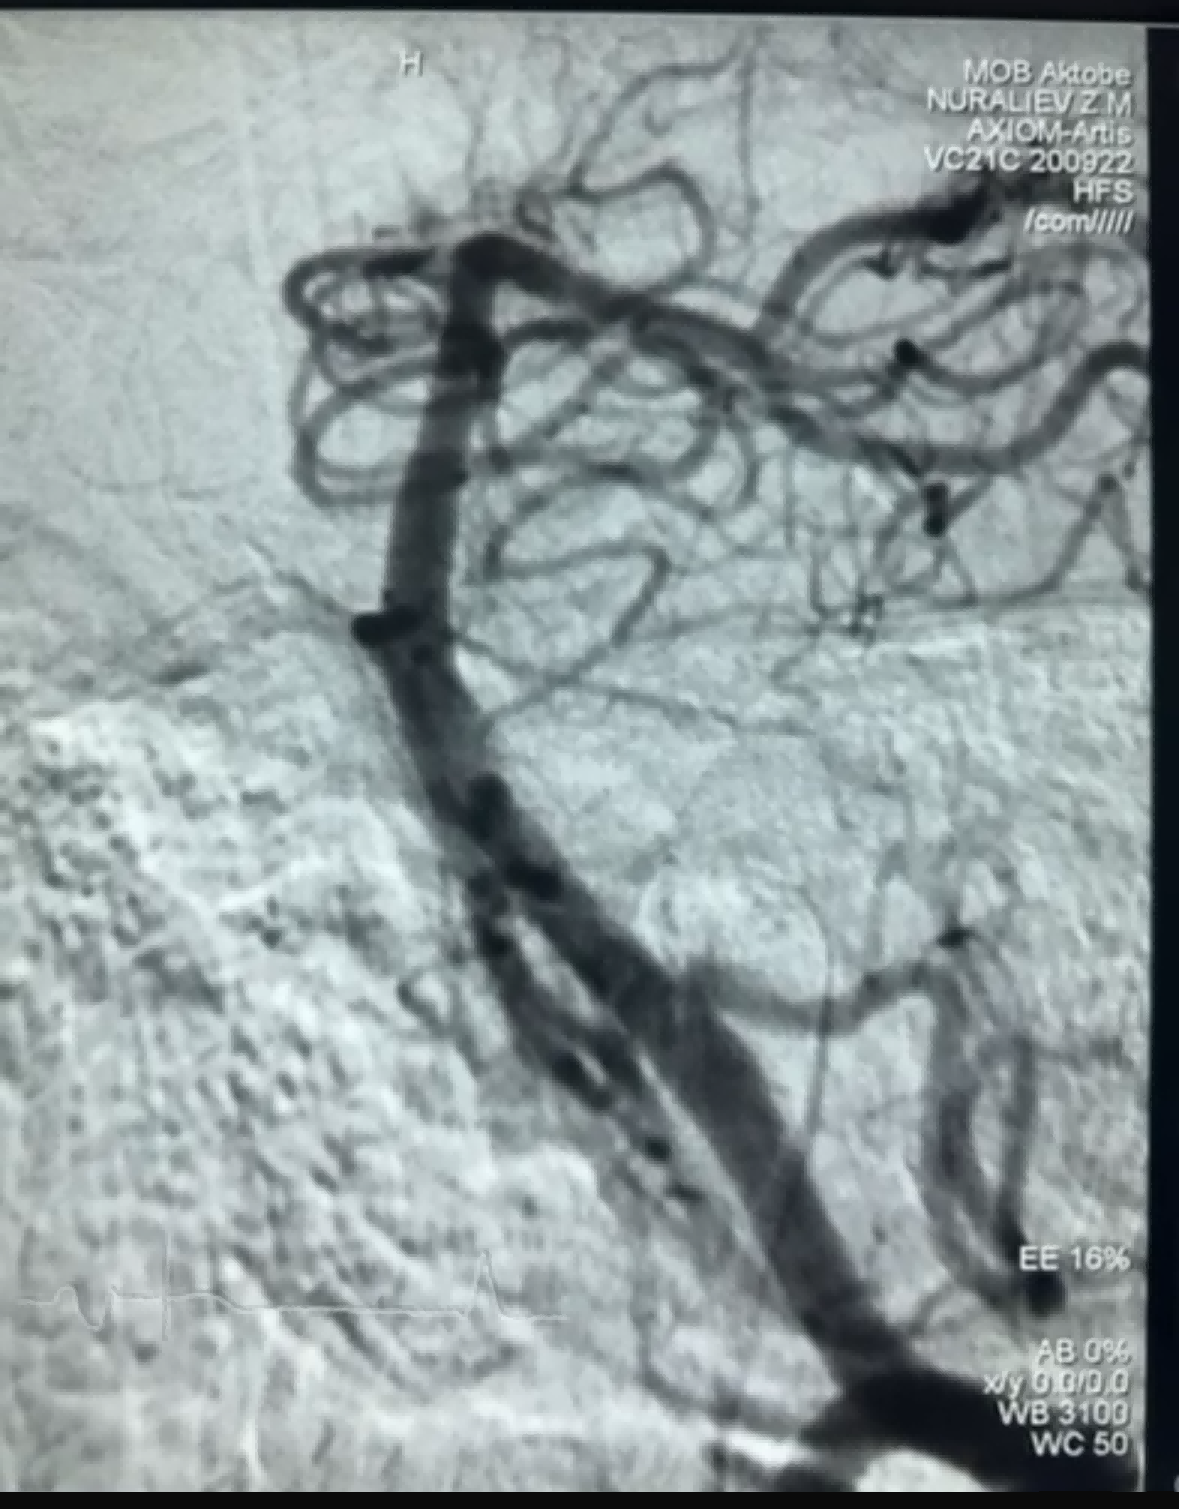

Yaqinda NeuroSafe Medical Co., Ltd kompaniyasining Dredger Stent Retriever yordamida muvaffaqiyatli trombektomiya ishi bo'ldi. Dredger Stent Retriever invaziv bo'lmagan yumshoq uchiga ega, bu esa intimal shikastlanish xavfini sezilarli darajada kamaytiradi va noyob maxsus shakldagi teshikka ega. asosan bo'shliq o'zgarishlar qisqich tomonidan qon quyqalarini ushlaydi dizayn.